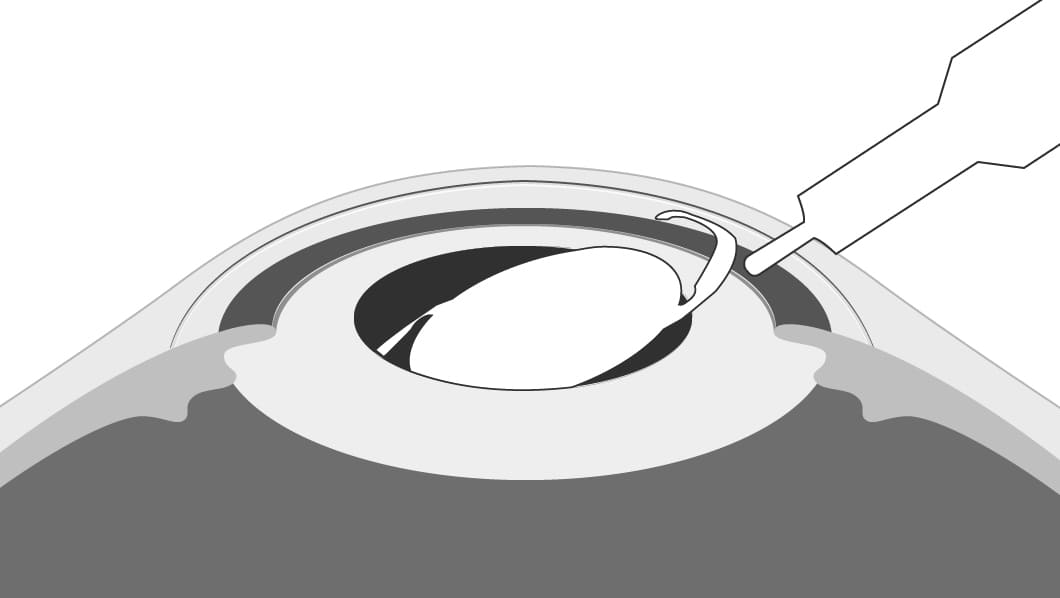

そのため、手術で水晶体を取り除き、代わりに「眼内レンズ」という人工のレンズを挿入し、見え方を改善します。

- 3眼内レンズを挿入します。

-